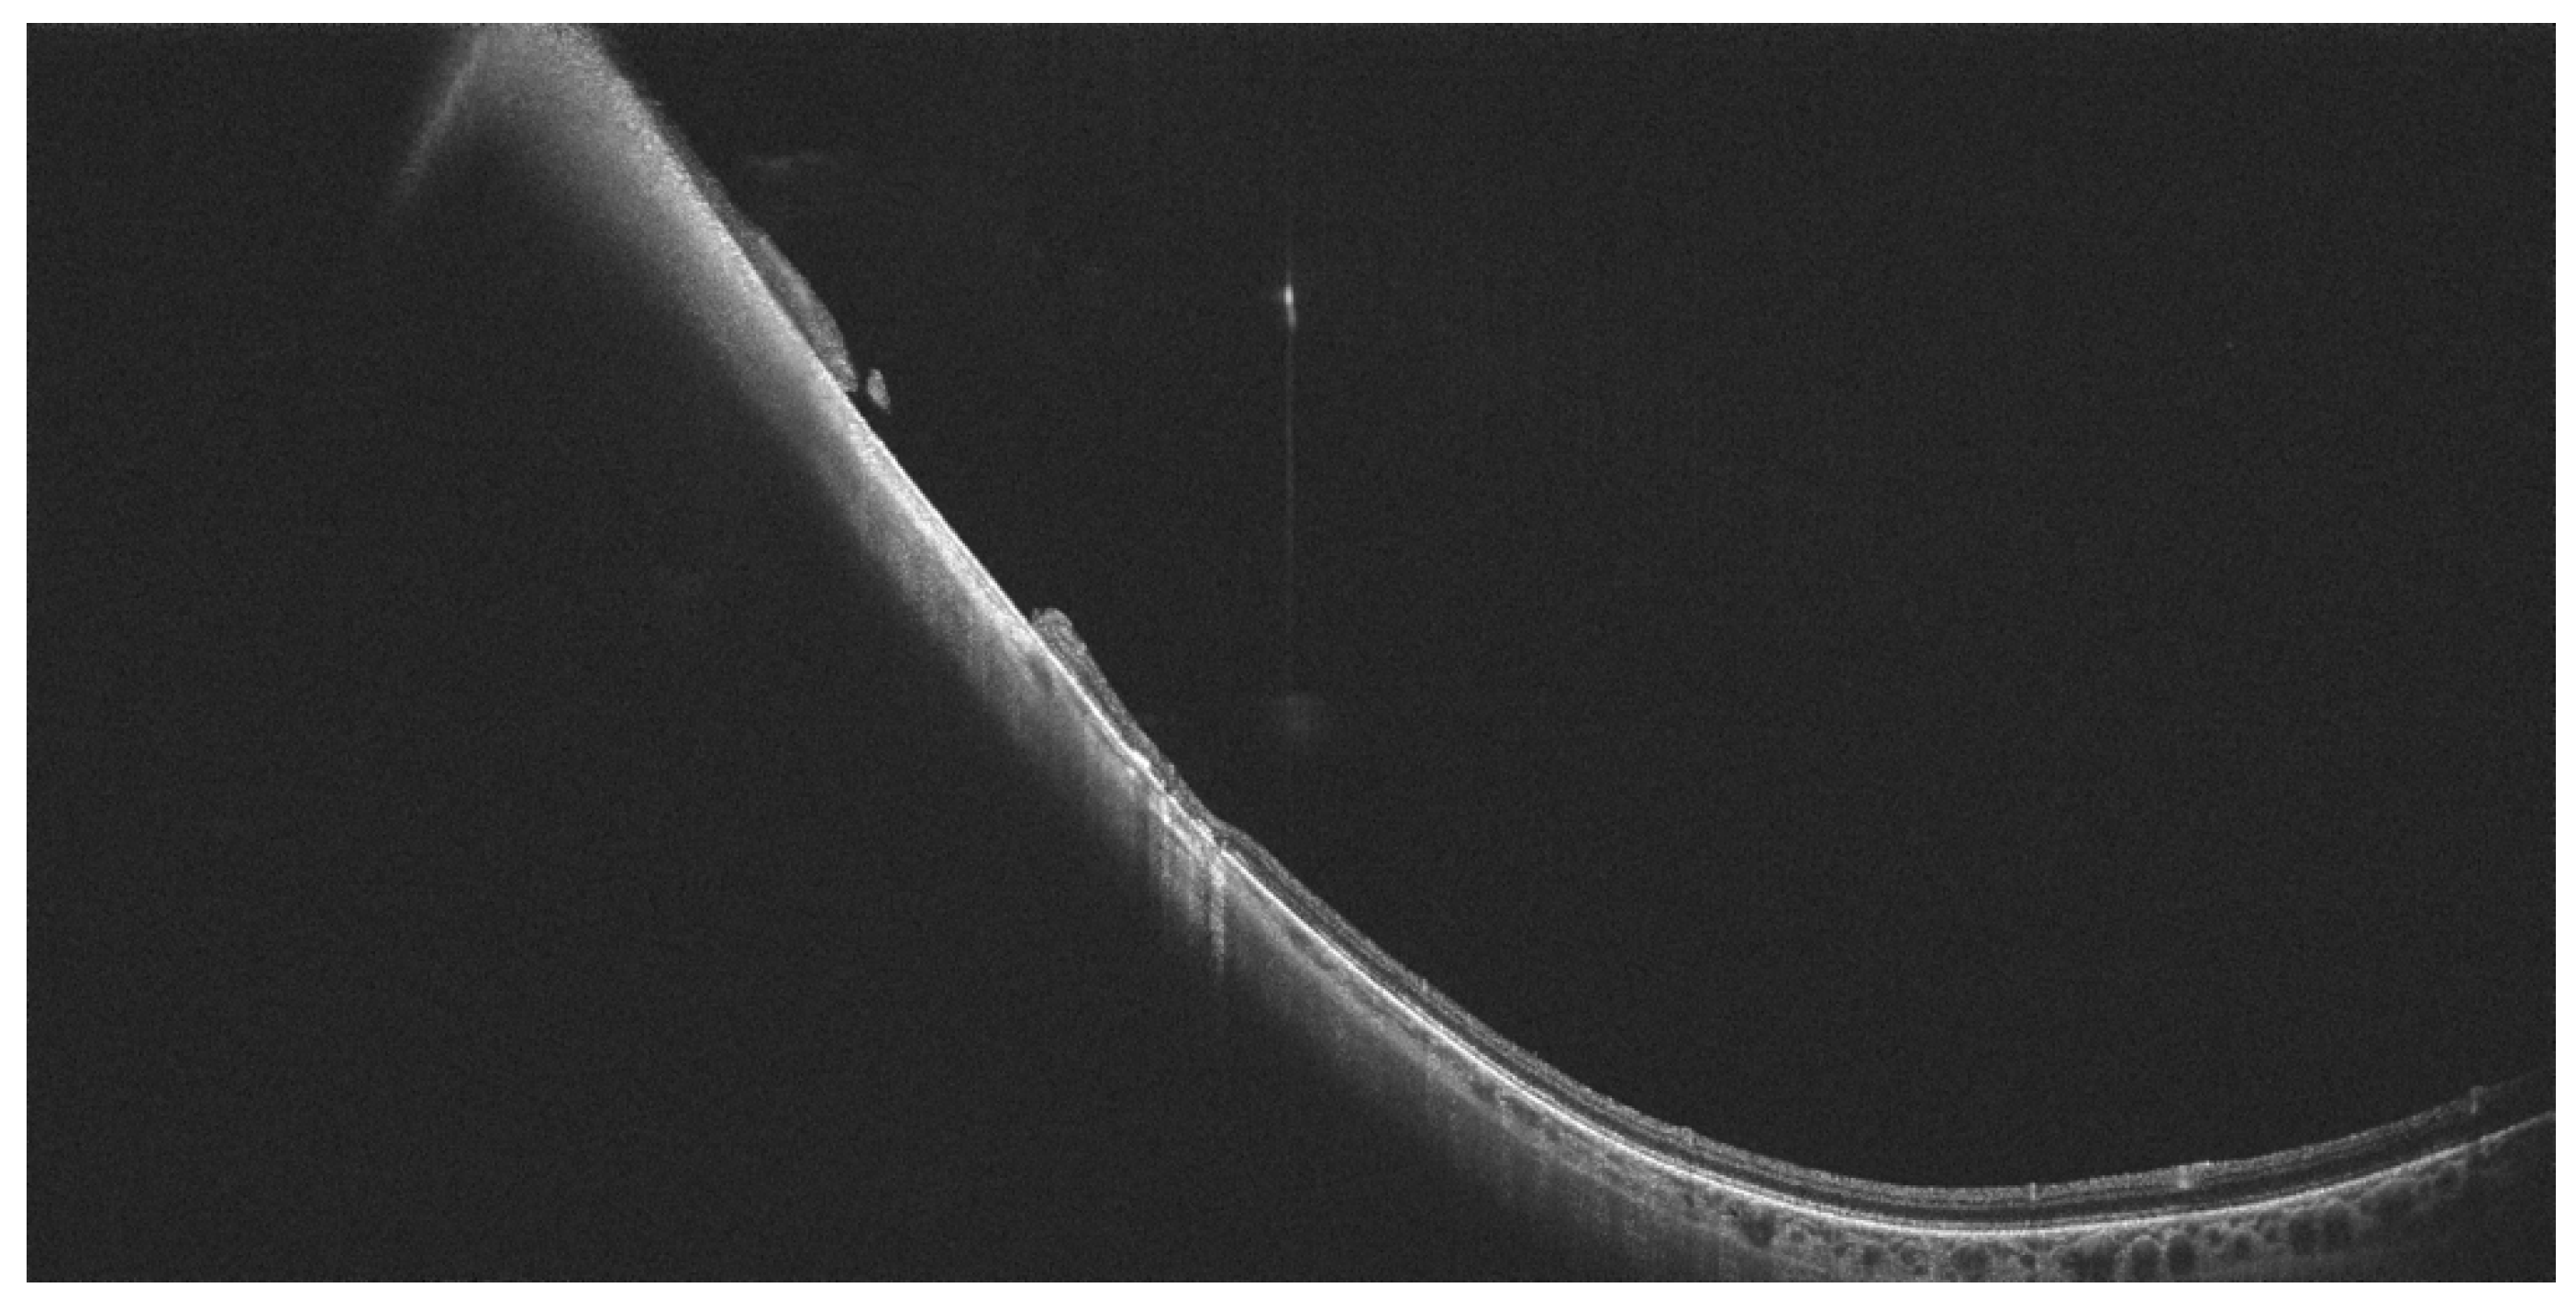

- Govetto, A.; Sebag, J.; Lucchini, S.; Ballabio, C.; Matteucci, M.; Ranno, S.; Carini, E.; Virgili, G.; Bacherini, D.; Radice, P. Imaging rhegmatogenous retinal lesions and peripheral vitreo-retinal interface with wide-field optical coherence tomography. Retina 2023, 44, 269–279. [Google Scholar] [CrossRef] [PubMed]

- Kurobe, R.; Hirano, Y.; Ogura, S.; Yasukawa, T.; Ogura, Y. Ultra-Widefield Swept-Source Optical Coherence Tomography Findings of Peripheral Retinal Degenerations and Breaks. Clin. Ophthalmol. 2021, 15, 4739–4745. [Google Scholar] [CrossRef] [PubMed]

- Stanga, P.E.; Pastor-Idoate, S.; Reinstein, U.; Vatas, P.; Patel, U.; Dubovy, S.; Reinstein, D.Z.; Zahavi, O. Navigated single-capture 3D and cross-sectional wide-field OCT of the mid and peripheral retina and vitreoretinal interface. Eur. J. Ophthalmol. 2022, 32, 1642–1651. [Google Scholar] [CrossRef] [PubMed]

- Tsukahara, M.; Mori, K.; Gehlbach, P.L.; Mori, K. Posterior Vitreous Detachment as Observed by Wide-Angle OCT Imaging. Ophthalmology 2018, 125, 1372–1383. [Google Scholar] [CrossRef] [PubMed]